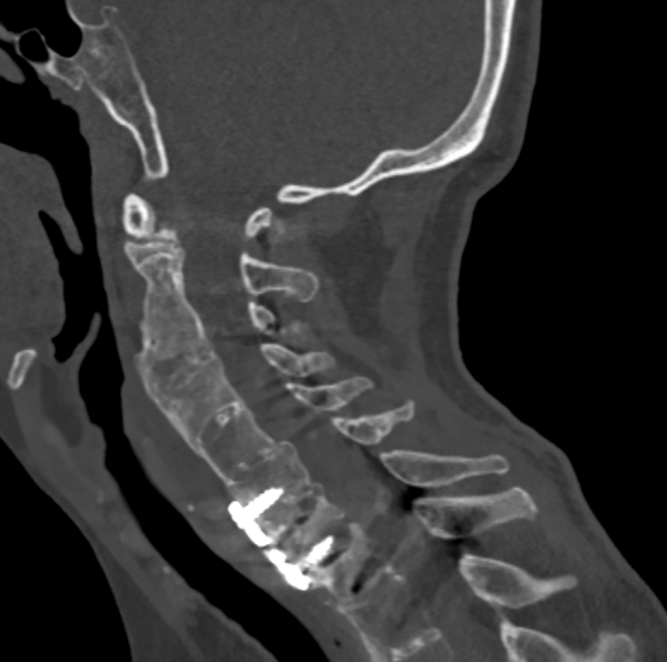

去年,家住昆山的金先生走路的时候不慎摔倒,下颌撞击硬物后感到颈部疼痛难忍,到当地医院查CT显示:(枢椎)齿状突骨折,骨折块向椎管方向移位。齿状突骨折属于上颈椎,位于头颅和颈椎的交界区域,是连接生命中枢的要塞,解剖结构复杂,有椎动脉和中枢神经从中穿过,稍有不慎就会引起大出血、瘫痪、甚至立即死亡。这类手术属于上颈椎手术,曾一度被视为骨科的手术禁区,国内仅有少数医院能够开展这一类手术,一般医师不敢轻易尝试。在业内医师的推荐下,家属送金先生来到了苏州大学附属独墅湖医院,找到了姜为民主任。

接诊后得知,金先生还患有强直性脊柱炎多年,这种疾病直接的后果是脊柱强直如棍棒,骨质变脆易骨折,被冠名以“不死的癌症”。姜主任详细了解金先生的病史后,认为该患者的治疗关键在于以下三个方面:一是脊柱强直,手术部位的位置深难以显露,解剖复杂。二是C2、C3左侧椎弓根发育异常狭小,置入椎弓根螺钉困难。三是齿状突骨折向后方移位明显,通常向前脱位较为常见复位也较容易,此种脱位的复位具有较大的难度和损伤脊髓的风险,对于术者而言是个巨大考验。

金先生伤后第7天,姜主任医师团队在麻醉手术科的密切配合下成功为他实施手术。姜主任凭借多年徒手置钉的过硬技术经验,2小时不到便完成了手术,术中出血仅100ml。术后CT显示齿状突完美复位,螺钉“不偏不倚”的位置恰到好处。术后,金先生在骨科护士长张霞芬护理团队的精心护理下,15天后伤口拆线康复出院。